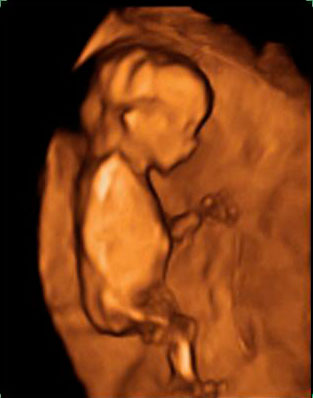

La imagen de esta ecografía en 4D de este embarazo muestra tres fetos, uno de ellos independiente, que está "aislado" de sus dos hermanos gemelos.

La ecografía en 4D no deja lugar a dudas: se trata de tres fetos, uno de ellos independiente (en la parte superior de la imágen), que está separado de sus hermanos gemelos por una membrana más gruesa. El embarazo gemelar está compuesto por dos fetos y dos bolsas, separadas por una fina membrana que apenas se aprecia en el vídeo. Los movimientos ecográficos nos permiten ver a las criaturas en diferentes planos.